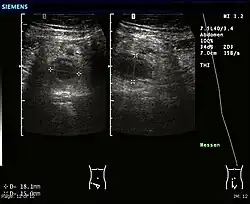

Abdominal ultrasonography, preferably with doppler sonography, is useful to detect appendicitis, especially in children. Ultrasound can show the free fluid collection in the right iliac fossa, along with a visible appendix with increased blood flow when using color Doppler, and noncompressibility of the appendix, as it is essentially a walled-off abscess. Other secondary sonographic signs of acute appendicitis include the presence of echogenic mesenteric fat surrounding the appendix and the acoustic shadowing of an appendicolith.[59] In some cases (approximately 5%),[60] ultrasonography of the iliac fossa does not reveal any abnormalities despite the presence of appendicitis. This false-negative finding is especially true of early appendicitis before the appendix has become significantly distended. Also, false-negative findings are more common in adults where larger amounts of fat and bowel gas make visualizing the appendix technically difficult. Despite these limitations, sonographic imaging with experienced hands can often distinguish between appendicitis and other diseases with similar symptoms. Some of these conditions include inflammation of lymph nodes near the appendix or pain originating from other pelvic organs such as the ovaries or Fallopian tubes. Ultrasounds may be either done by the radiology department or by the emergency physician.[61]

Ultrasound showing appendicitis and an appendicolith.[62]

Ultrasound showing appendicitis and an appendicolith.[62] -

Ultrasound of a normal appendix for comparison. -

A normal appendix without and with compression. Absence of compressibility indicates appendicitis.[59]